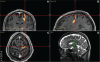

Parkinson's disease (PD) is marked by excessive synchronous activity in the beta (8-35 Hz) band throughout the cortico-basal ganglia network. The optimal location of high frequency deep brain stimulation (HF DBS) within the subthalamic nucleus (STN) region and the location of maximal beta hypersynchrony are currently matters of debate. Additionally, the effect of STN HF DBS on neural synchrony in functionally connected regions of motor cortex is unknown and is of great interest. Scalp EEG studies demonstrated that stimulation of the STN can activate motor cortex antidromically, but the spatial specificity of this effect has not been examined. The present study examined the effect of STN HF DBS on neural synchrony within the cortico-basal ganglia network in patients with PD. We measured local field potentials dorsal to and within the STN of PD patients, and additionally in the motor cortex in a subset of these patients. We used diffusion tensor imaging (DTI) to guide the placement of subdural cortical surface electrodes over the DTI-identified origin of the hyperdirect pathway (HDP) between motor cortex and the STN. The results demonstrated that local beta power was attenuated during HF DBS both dorsal to and within the STN. The degree of attenuation was monotonic with increased DBS voltages in both locations, but this voltage-dependent effect was greater in the central STN than dorsal to the STN (p < 0.05). Cortical signals over the estimated origin of the HDP also demonstrated attenuation of beta hypersynchrony during DBS dorsal to or within STN, whereas signals from non-specific regions of motor cortex were not attenuated. The spatially-specific suppression of beta synchrony in the motor cortex support the hypothesis that DBS may treat Parkinsonism by reducing excessive synchrony in the functionally connected sensorimotor network.